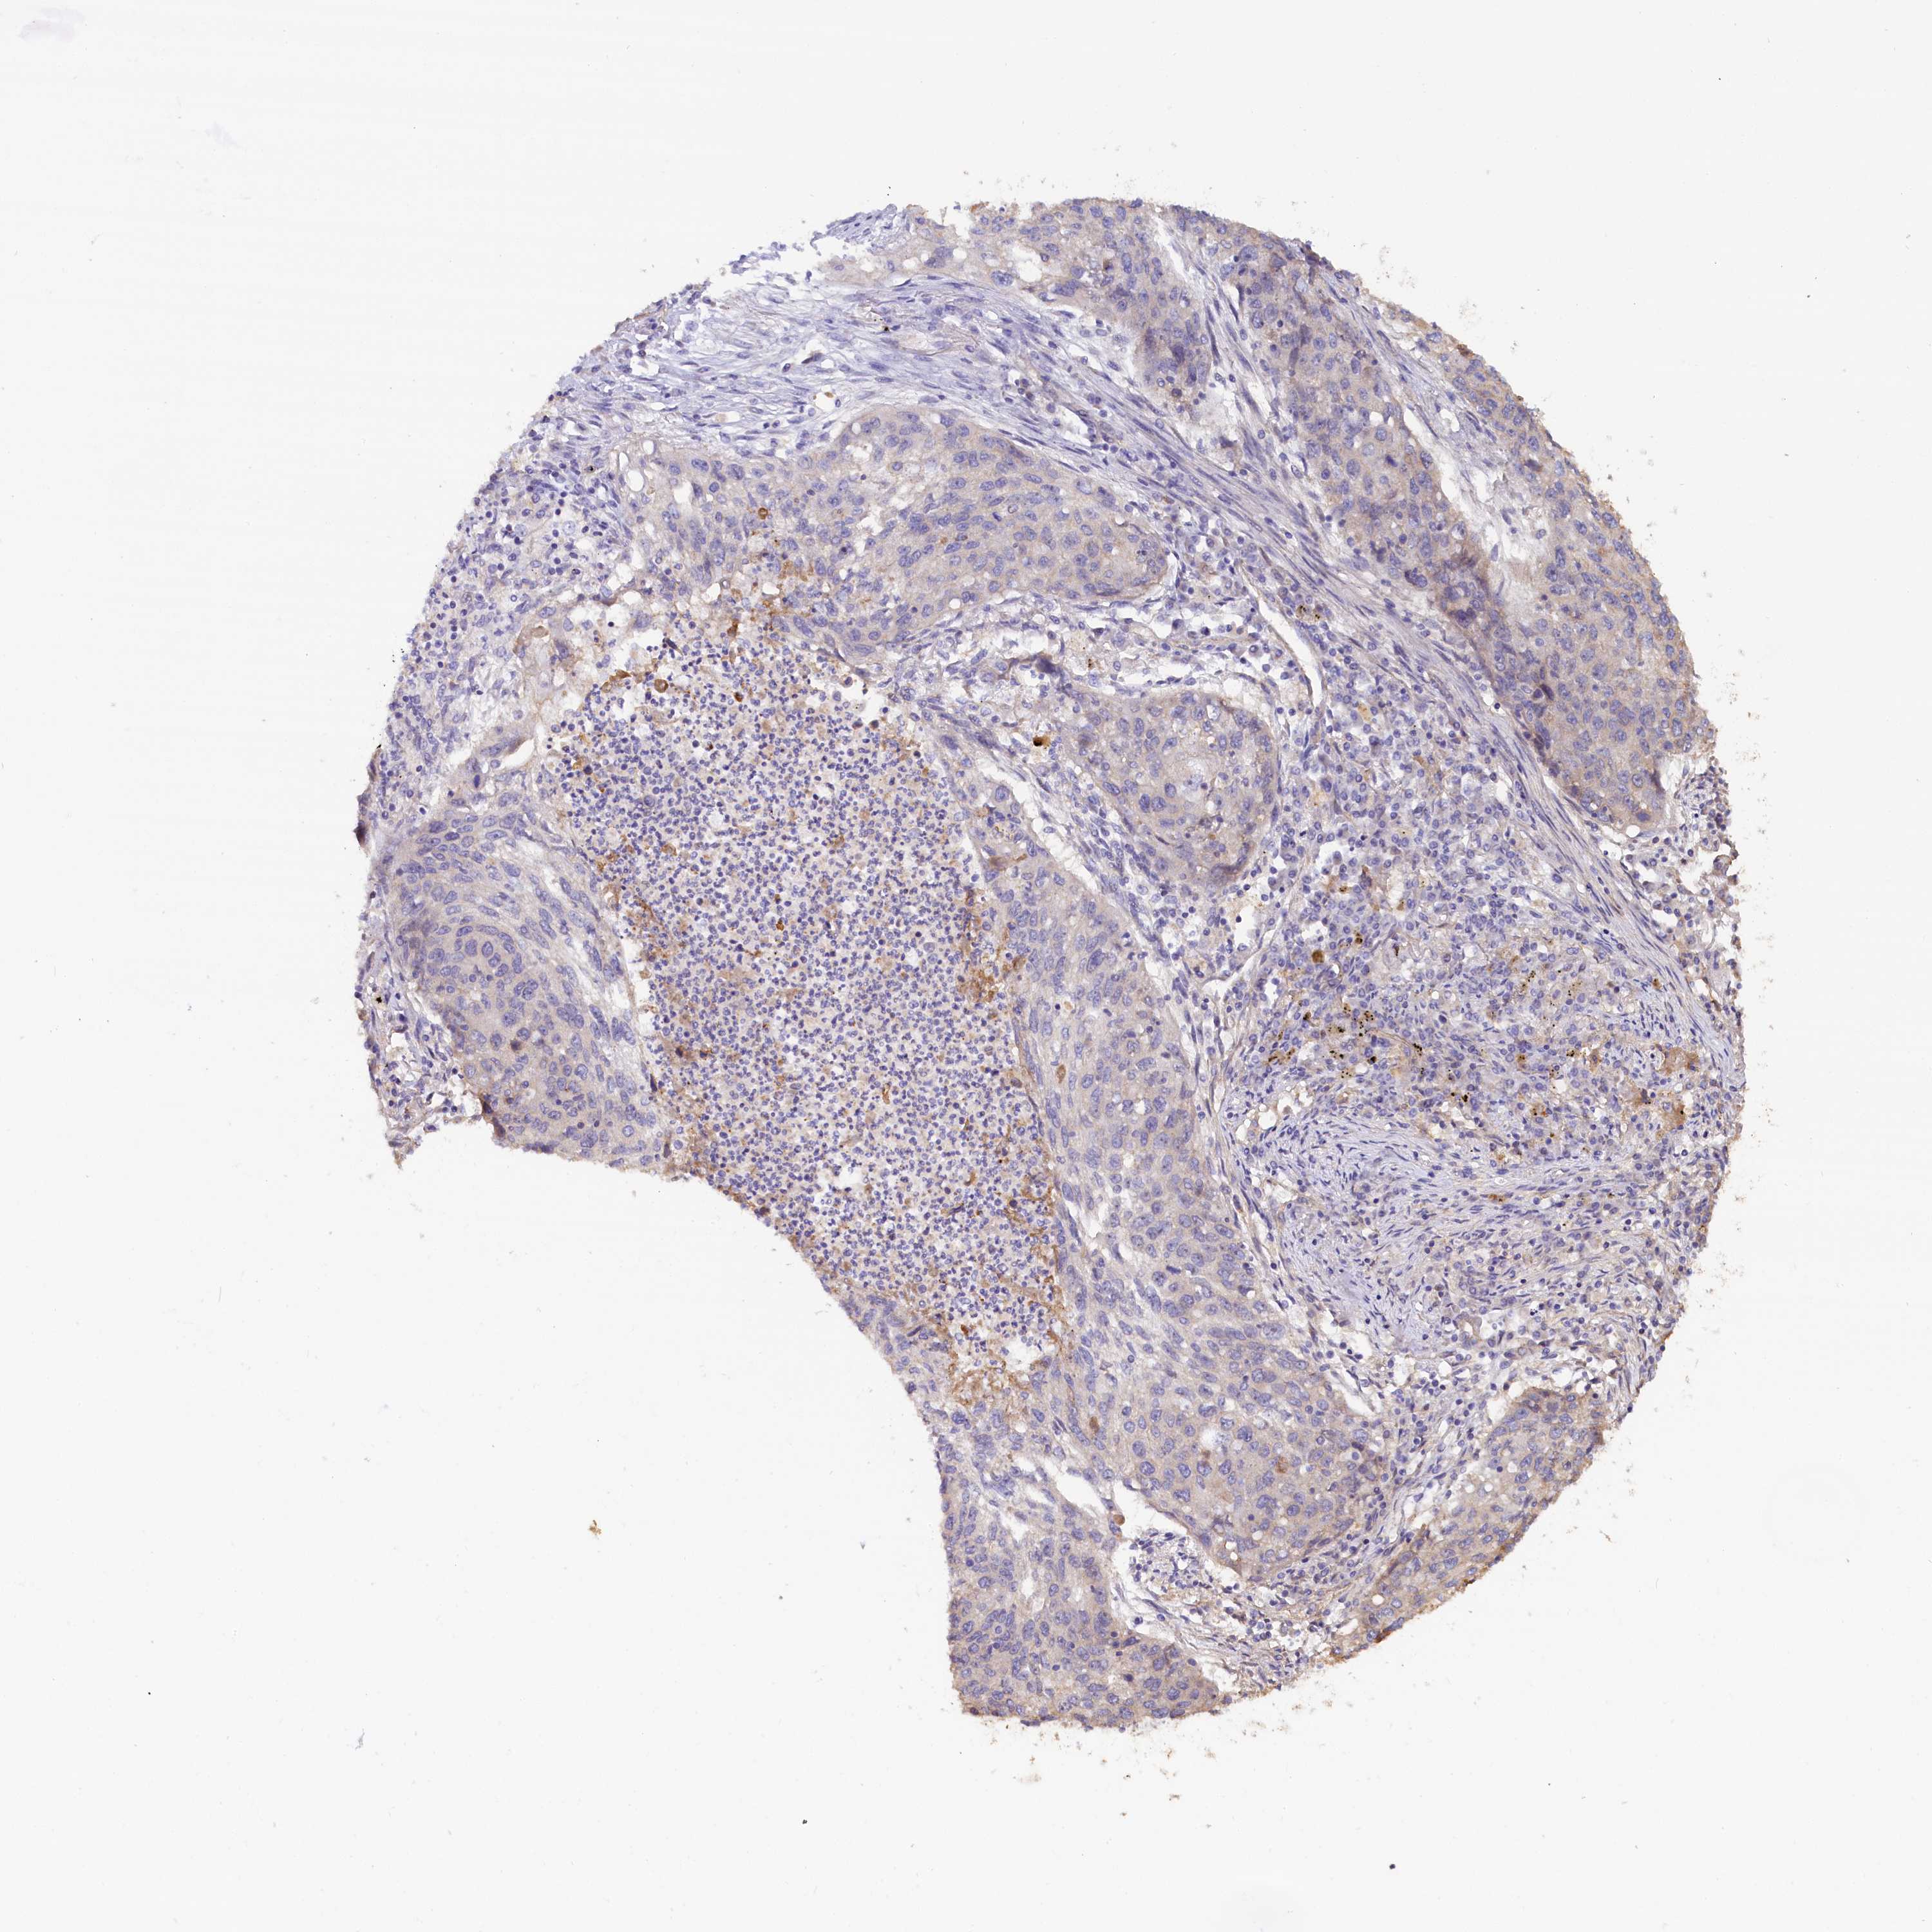

LUNG ADENOCARCINOMA (VALIDATION) - Interactive survival scatter ploti

The Survival Scatter plot shows the clinical status (i.e. dead or alive) for all individuals in the patient cohort, based on the same data that underlies the corresponding Kaplan-Meier plots. Patients that are alive at last time for follow-up are shown in blue and patients who have died during the study are shown in red.

The x-axis shows the expression levels (FPKM) of the investigated gene in the tumor tissue at the time of diagnosis. The y-axis shows the follow-up time after diagnosis (years). Both axes are complimented with kernel density curves demonstrating the data density over the axes. The top density plot shows the expression levels (FPKM) distribution among dead (red) and alive patients (blue). The right density plot shows the data density of the survived years of dead patients with high and low expression levels respectively, stratified using the cutoff indicated by the vertical dashed line through the Survival Scatter plot. This cutoff is automatically defined based on the FPKM cutoff that minimizes the p-score. The cutoff can be changed by dragging the vertical line or by entering a cutoff value in the square labeled "Current cut-off".

Under the Survival Scatter plot the p-score landscape (black curve; left axis) is shown together with dead median separation (red curve; right axis). Dead median separation is the difference in median mRNA expression between patients who have died with high and low expression, respectively. It is calculated as follows: median FPKM expression of dead patients with high expression - median FPKM expression of dead patients with low expression. This is intended to aid the user in visually exploring custom cutoffs and the associated p-scores and dead median separation.

Individual patient data is displayed and can be filtered by clicking on one or more of the category buttons on the top of the page. Categories describing expression level and patient information include: high, low, alive, dead, female, male and tumor stages. The scale of the x-axis can be toggled between linear and log-scale by clicking on the "x log" button. Mouse-over function shows TCGA ID, patient information and mRNA expression (FPKM) for each patient.

& Survival analysisi

Kaplan-Meier plots summarize results from analysis of correlation between mRNA expression level and patient survival. Patients were divided based on level of expression into one of the two groups "low" (under cut off) or "high" (over cut off). X-axis shows time for survival (years) and y-axis shows the probability of survival, where 1.0 corresponds to 100 percent.

KATNB1 is not prognostic in Lung Adenocarcinoma (validation)

: 5.65